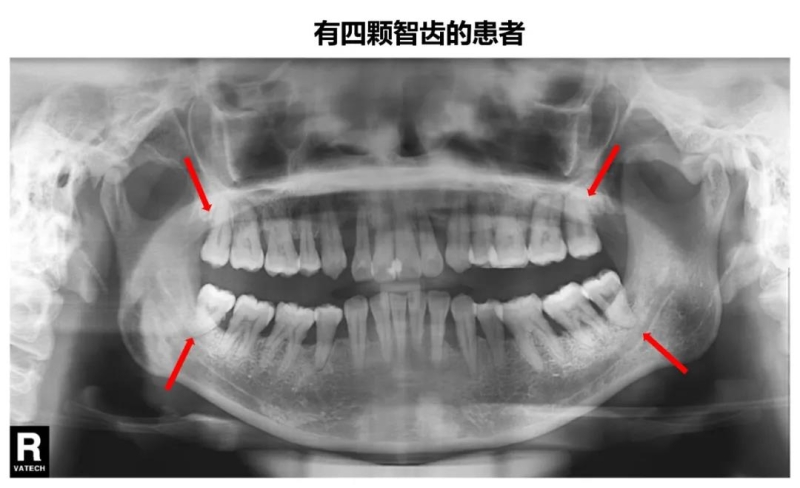

8、除了第3磨牙与多生牙,一般成人拔牙后均需安装假牙,大约拔牙后3个月左右应修复,以避免邻牙倒伏,从而在牙列中引发多米诺骨牌效应!